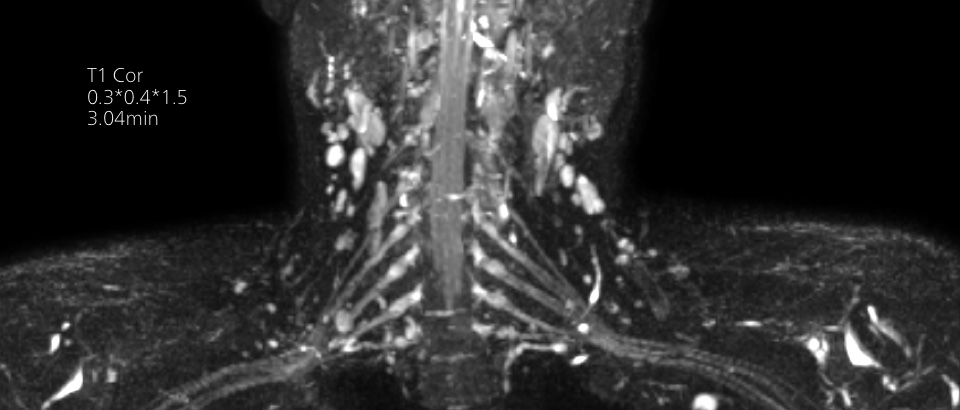

Our lightest Breeze coils bring versatility and create consistent high quality images for any anatomy.

Our lightest Breeze coils bring extraordinary versatility to imaging challenging anatomies and the smallest joints. A large 55cm field-of-view and premium SNR add to the exceptional image quality.